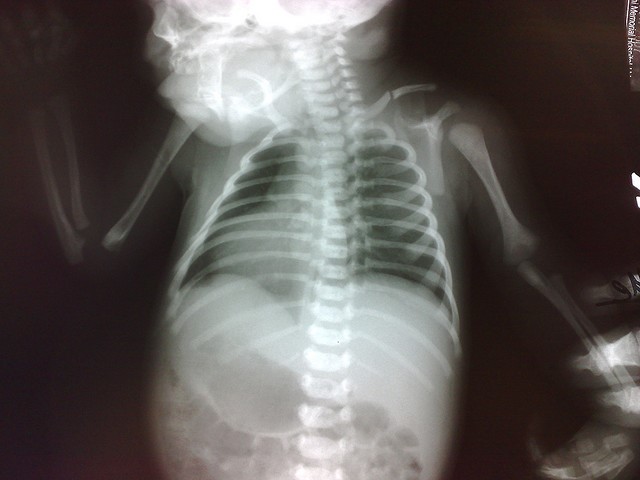

Чтобы определить тип повреждения, наличие смещения обломков и уточнить терапевтическую тактику, назначают рентген верхней части груди. Если постановка диагноза затруднена, то травматолог назначает компьютерную томографию или МРТ ключицы.

Так выглядит рентгеновский снимок перелома ключицы у ребёнка

Если же возникает подозрение на повреждение вен или артерий, нервных пучков, потребуется осмотр сосудистого хирурга, специалиста в нейрохирургии и доктора, который занимается лечением органов грудной клетки.